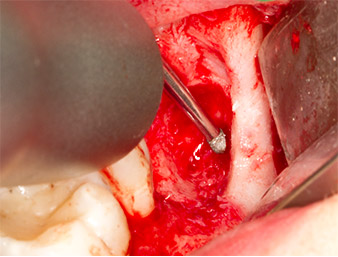

To expose the root remnant with as little trauma as possible to the tissue, a further instrument was used (Piezomed S2) that is primarily indicated for preparing the lateral window in augmentations of the sinus floor. The diamond-coated ball was additionally used to smooth sharp bone edges (Fig. 6 and 7). All the Piezomed attachments were used with the relevant automatic default setting without booster function.

Piezomed S2

Fig. 6: The root remnant is carefully exposed with a diamond-coated spherical instrument (Piezomed S2), bone edges are smoothed.

Using an instrument for periodontal debridement (Piezomed P1), the periodontal ligament space of the radix relicta was then widened minimally (Fig. 8).

The same activated instrument was inserted into the root canal and loosened the fragment as a result of its micro-oscillating vibrations (Fig. 9, 10).